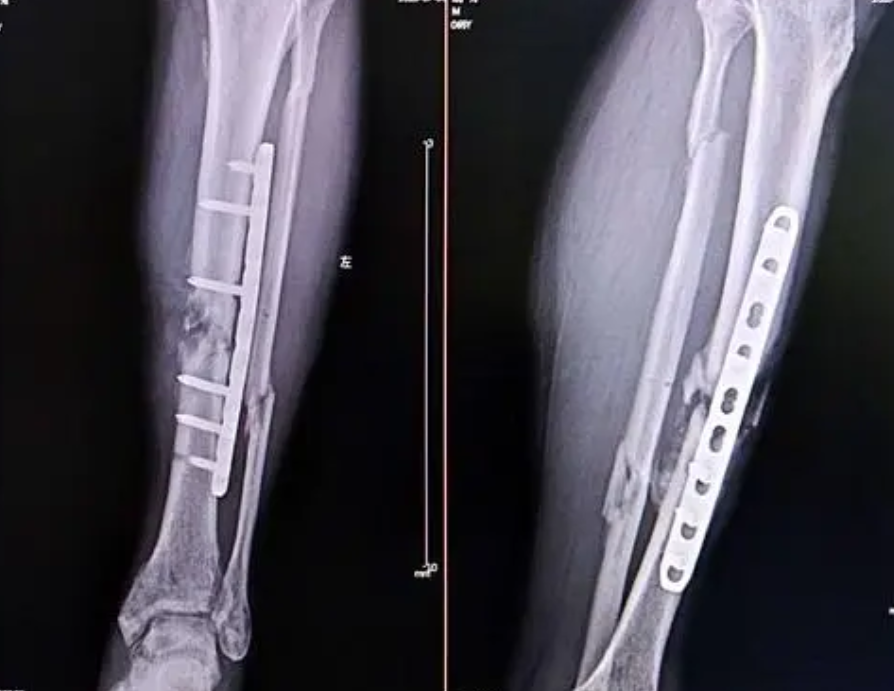

骨缺损骨折发生于胫骨占68%,股骨占22%,其他部位约为10%。骨干是发生骨缺损的常见部位,当发生骨缺损时候,手术是骨缺损采取的方法。具体来说有三种: